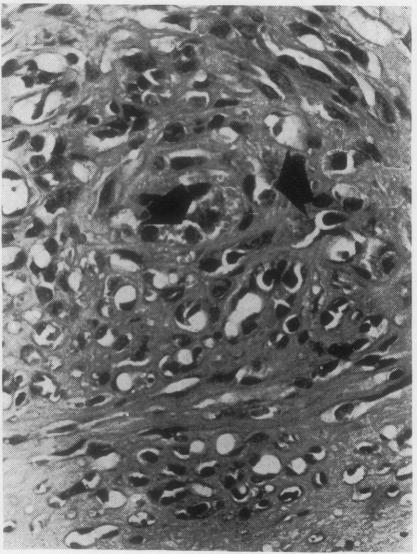

A comparison has been made between two vasoformative lesions, Kaposi's sarcoma and granuloma pyogenicum, as they are encountered in Uganda. Both are predominantly skin lesions arising in the distal extremities, may resemble each other clinically, and are widespread in their distribution in Ugandan communities. They bear a reciprocal relationship to each other as regards age and sex incidence, Kaposi's sarcoma being mainly a disease of adult males and granuloma pyogenicum a disease of immature males and females. Histologically there are many similarities between them, the essential difference being the presence of a spindle-cell sarcomatous element in Kaposi's sarcoma. The clinical behaviour reflects this difference in that granuloma pyogenicum develops quickly and appears to be self-limiting, while Kaposi's sarcoma is slowly progressive and shows much less tendency to regress. On the basis of these findings it is concluded that, although these two lesions may be completely unrelated, it is possible that both represent a response of the vasoformative elements in the skin to a similar form of initiating stimulus and that hormonal or sex-linked genetic factors determine which lesion will develop in response to this stimulus. The presence of intracytoplasmic inclusion in the tumour cells of Kaposi's sarcoma might be of significance in the histogenesis of this tumour, and of value in its histological differentiation from granuloma pyogenicum.

对乌干达出现的两种血管形成性病变——卡波西肉瘤和脓性肉芽肿进行了比较。两者主要都是发生在四肢远端的皮肤病变,在临床上可能彼此相似,并且在乌干达社区中分布广泛。它们在年龄和性别发病率方面呈反比关系,卡波西肉瘤主要是成年男性的疾病,而脓性肉芽肿是未成年男性和女性的疾病。组织学上它们有许多相似之处,本质区别在于卡波西肉瘤中存在梭形细胞肉瘤成分。临床行为反映了这种差异,脓性肉芽肿发展迅速且似乎有自限性,而卡波西肉瘤进展缓慢且消退倾向小得多。基于这些发现得出结论,尽管这两种病变可能完全无关,但两者都有可能代表皮肤血管形成成分对类似形式的起始刺激的反应,并且激素或性连锁遗传因素决定了对这种刺激会产生哪种病变。卡波西肉瘤肿瘤细胞中胞质内包涵体的存在可能对该肿瘤的组织发生具有重要意义,并且在其与脓性肉芽肿的组织学鉴别中具有价值。